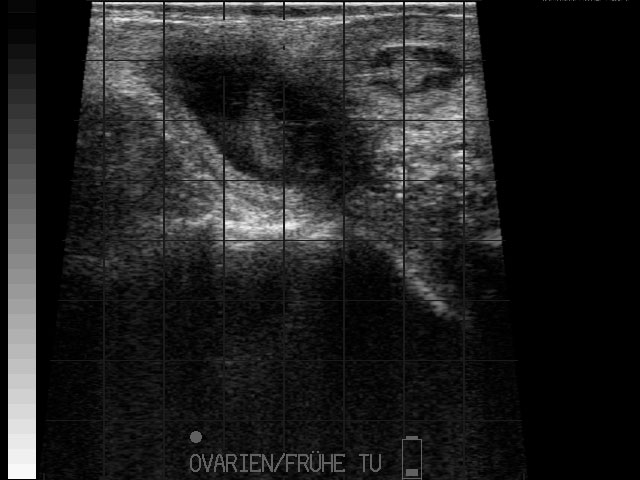

Eierstockstumor

Frühe Resorption